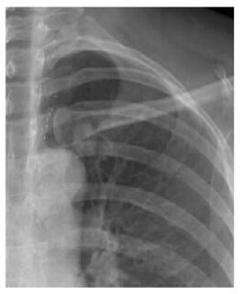

案例二:

圖二 左鎖骨重疊致密結(jié)節(jié),誤為衣服紐扣,病理肺腺癌

案例解析:

該病例發(fā)生在國(guó)內(nèi)某基層醫(yī)院,病患首先通過胸片攝影篩查,顯示出左上肺野內(nèi)帶高密度橢圓形結(jié)節(jié),由于形狀與紐扣極為相似,誤為衣服紐扣,并未做進(jìn)一步診斷。第二年之后,病患再來復(fù)查,卻發(fā)現(xiàn)照片上結(jié)節(jié)影增大,立即進(jìn)一步診斷檢查,最終經(jīng)過活檢證實(shí)為肺癌,錯(cuò)過了最佳的肺癌治療期。